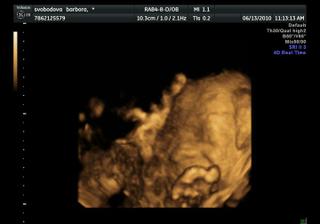

Náše bábetko a pupík🙂

Po 4 a půl letech jsme se rozhodli, že je nejvyšší čas pořídit si ten nejkrásnější dáreček 🙂 Po dvou snaženíčkách na nás vykoukly vytoužené //.